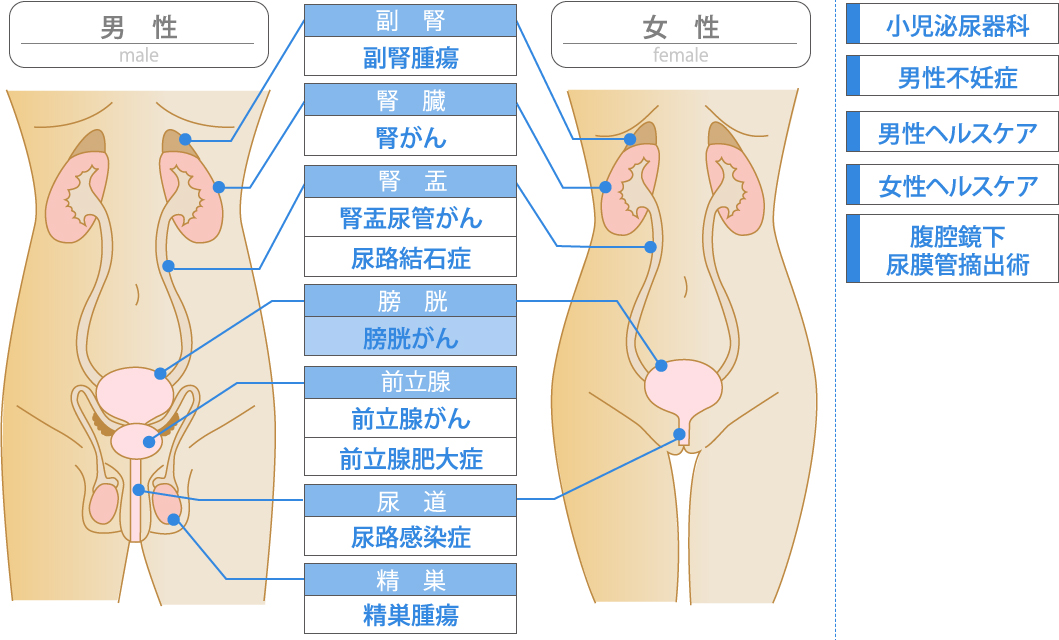

究める鏡視下膀胱全摘術・尿路変向術 Level up LRC, RARC | 三木。メジカルビュー社|泌尿器科|究める鏡視下膀胱全摘術・尿路変向。ロボット支援膀胱全摘除術(RARC) | 岩手医科大学 泌尿器科学講座。★3月精米★ 令和6年産 福井県産 いちほまれ 5kg 白米 精米。膀胱がん【泌尿器科疾患について】 - 東京慈恵会医科大学 泌尿器科。膀胱がん|KOMPAS。手術手技(膀胱全摘除術) | 領域情報 | アステラスメディカルネット。膀胱がん|KOMPAS。周術期の負担を軽減し早期社会復帰を!「ロボット支援腹腔鏡下。腎盂尿管移行部狭窄症に対するロボット支援腹腔鏡下腎盂形成術。朝倉書店『内科学』(第12版)デジタル付録。腹腔鏡下尿膜管摘出術及び左腎摘出術 - Olympus Professional。ロボット手術の定番!新品、未使用です。間違って2冊買ってしまったので、ページを開いてもいないため、本屋さんの「売上スリップ」も付いたままの全くの新品です。膀胱がんの外科治療について | 小野薬品 がん情報 一般向け。